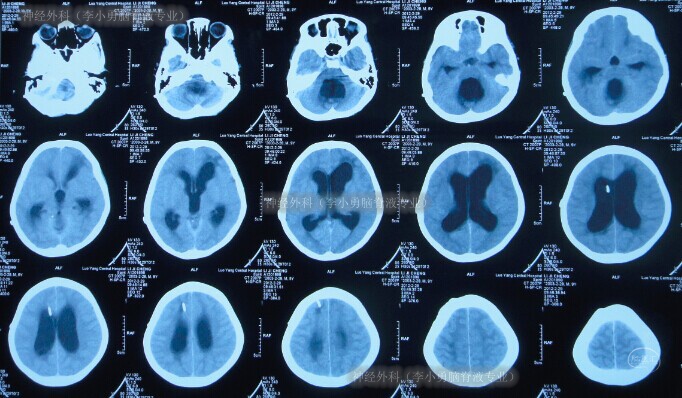

第1次分流术后第6年即2012年2月29日(10岁时),无明显诱因突然出现呕吐、腹部膨隆;急诊第2次就诊于第1家医院:河南省洛阳市某医院,查头颅CT显示脑室系统显著扩大,且第四脑室也显著扩大(图-1),脑积水复发。

图-1:2012年2月29日头颅CT